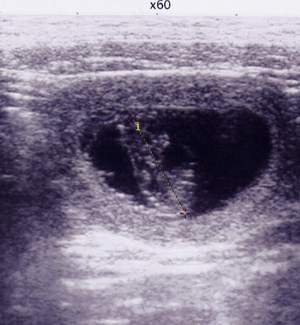

1. L’échographie : l’examen de référence dès J21

L’échographie est aujourd’hui l’examen le plus utilisé pour le diagnostic précoce de gestation chez la chienne. Elle permet de :

- détecter les ampoules fœtales à partir du 21e jour après la saillie ;

- visualiser les battements cardiaques fœtaux et donc évaluer la vitalité des chiots ;

- estimer le nombre de fœtus, même si ce comptage n’est pas aussi précis qu’avec la radiographie ;

- suivre l’évolution de la gestation tout au long des deux mois.

Fiabilité : Elle est très bonne à partir de J21–J25, à condition que l’examen soit réalisé par un vétérinaire expérimenté et que la chienne soit coopérative. Une chienne agitée, tendue, ou des intestins mal positionnés peuvent réduire la lisibilité de l’image et entraîner des erreurs d’interprétation. Si le résultat semble douteux, il ne faut pas hésiter à demander un second avis ou à répéter l’examen quelques jours plus tard.

Innocuité : L’échographie n’émet pas de rayonnement ionisant. Elle est sans danger pour la chienne et pour les fœtus.

Coût approximatif : entre 45 et 80 € selon les cliniques (France / Belgique), examen de base sans suivi particulier.